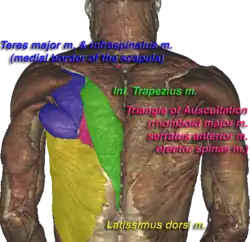

Triangle of auscultation (shown in pink) of the Visible Human Male | |

The triangle of auscultation is a relative thinning of the musculature of the back, situated along the medial border of the scapula which allows for improved listening to the lungs.

Boundaries

It has the following boundaries:

- medially, by the inferior portion of the trapezius

- inferiorly, by the latissimus dorsi

- laterally, by the medial border of the scapula

The superficial floor of the triangle is formed by the lateral portion of the erector spinae muscles. Deep to these muscles are the osseous portions of the 6th and 7th ribs and the internal and external intercostal muscles.